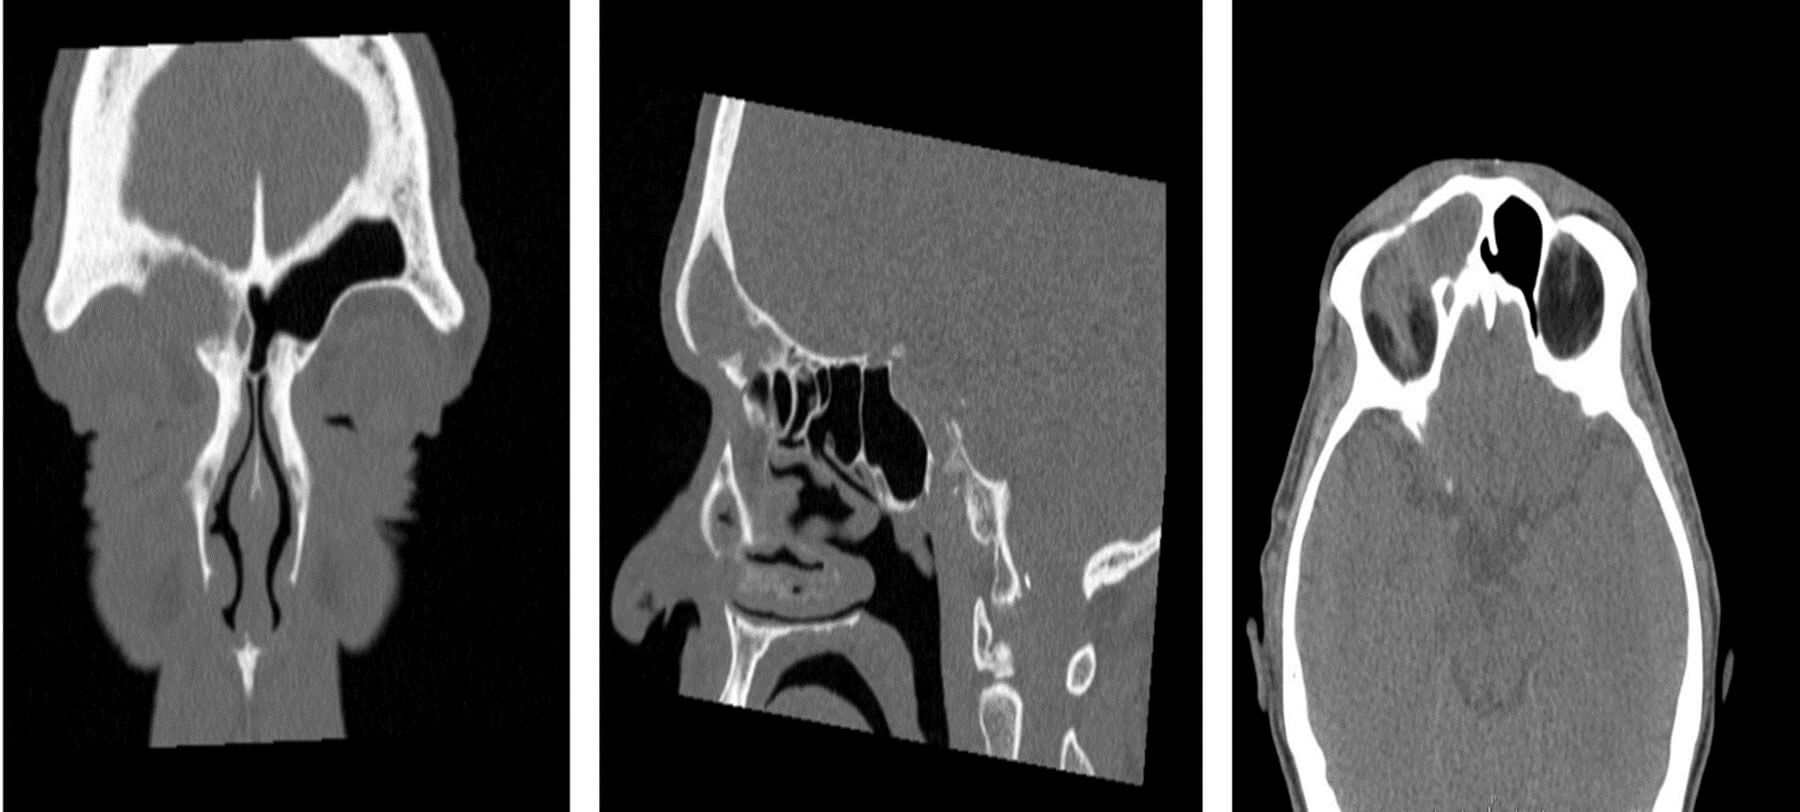

Figure 3:

Figure 3a (far left): CT scan - Coronal cut showing complete opacification

of the right frontal sinus with a large bone defect in the orbital roof.

Figure 3b (middle): CT scan - Sagittal cut showing the expansion of the

frontal sinus and erosion of the orbital roof anteriorly and posteriorly.

Figure 3c (far right): CT scan - Axial cut showing herniation of some of the frontal

sinus content into the orbital cavity via the bony defect in the orbital roof.

Histopathology report showed inflammatory changes, and no evidence of atypia or malignancy. The culture was negative for any infection. Postoperative CT scans showed: a large FOM, with erosion of the orbital roof and formation of a cutaneous fistula in the upper eyelid area, and herniation of some of the sinus content into the orbit. There was also a fine lucent defect extending the frontal sinus roof into the floor of the anterior cranial fossa with no evidence of subdural empyema (Figures 3a, 3b, 3c).